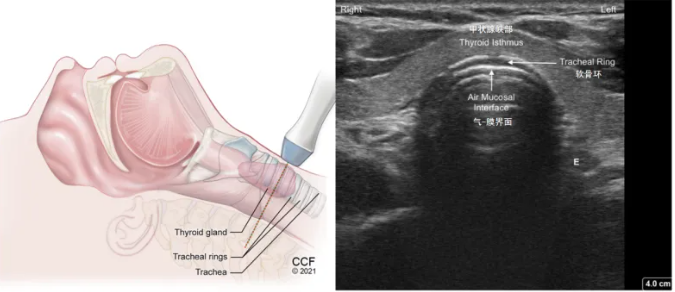

(5)气管软骨环横切面(图13):探头再往下就看到一个等回声或低回声结构,即为甲状腺的峡部,在进行气管切开操作时,需要进行定位,以免出现误穿和损伤。

image.png

图13 气管软骨环横切面